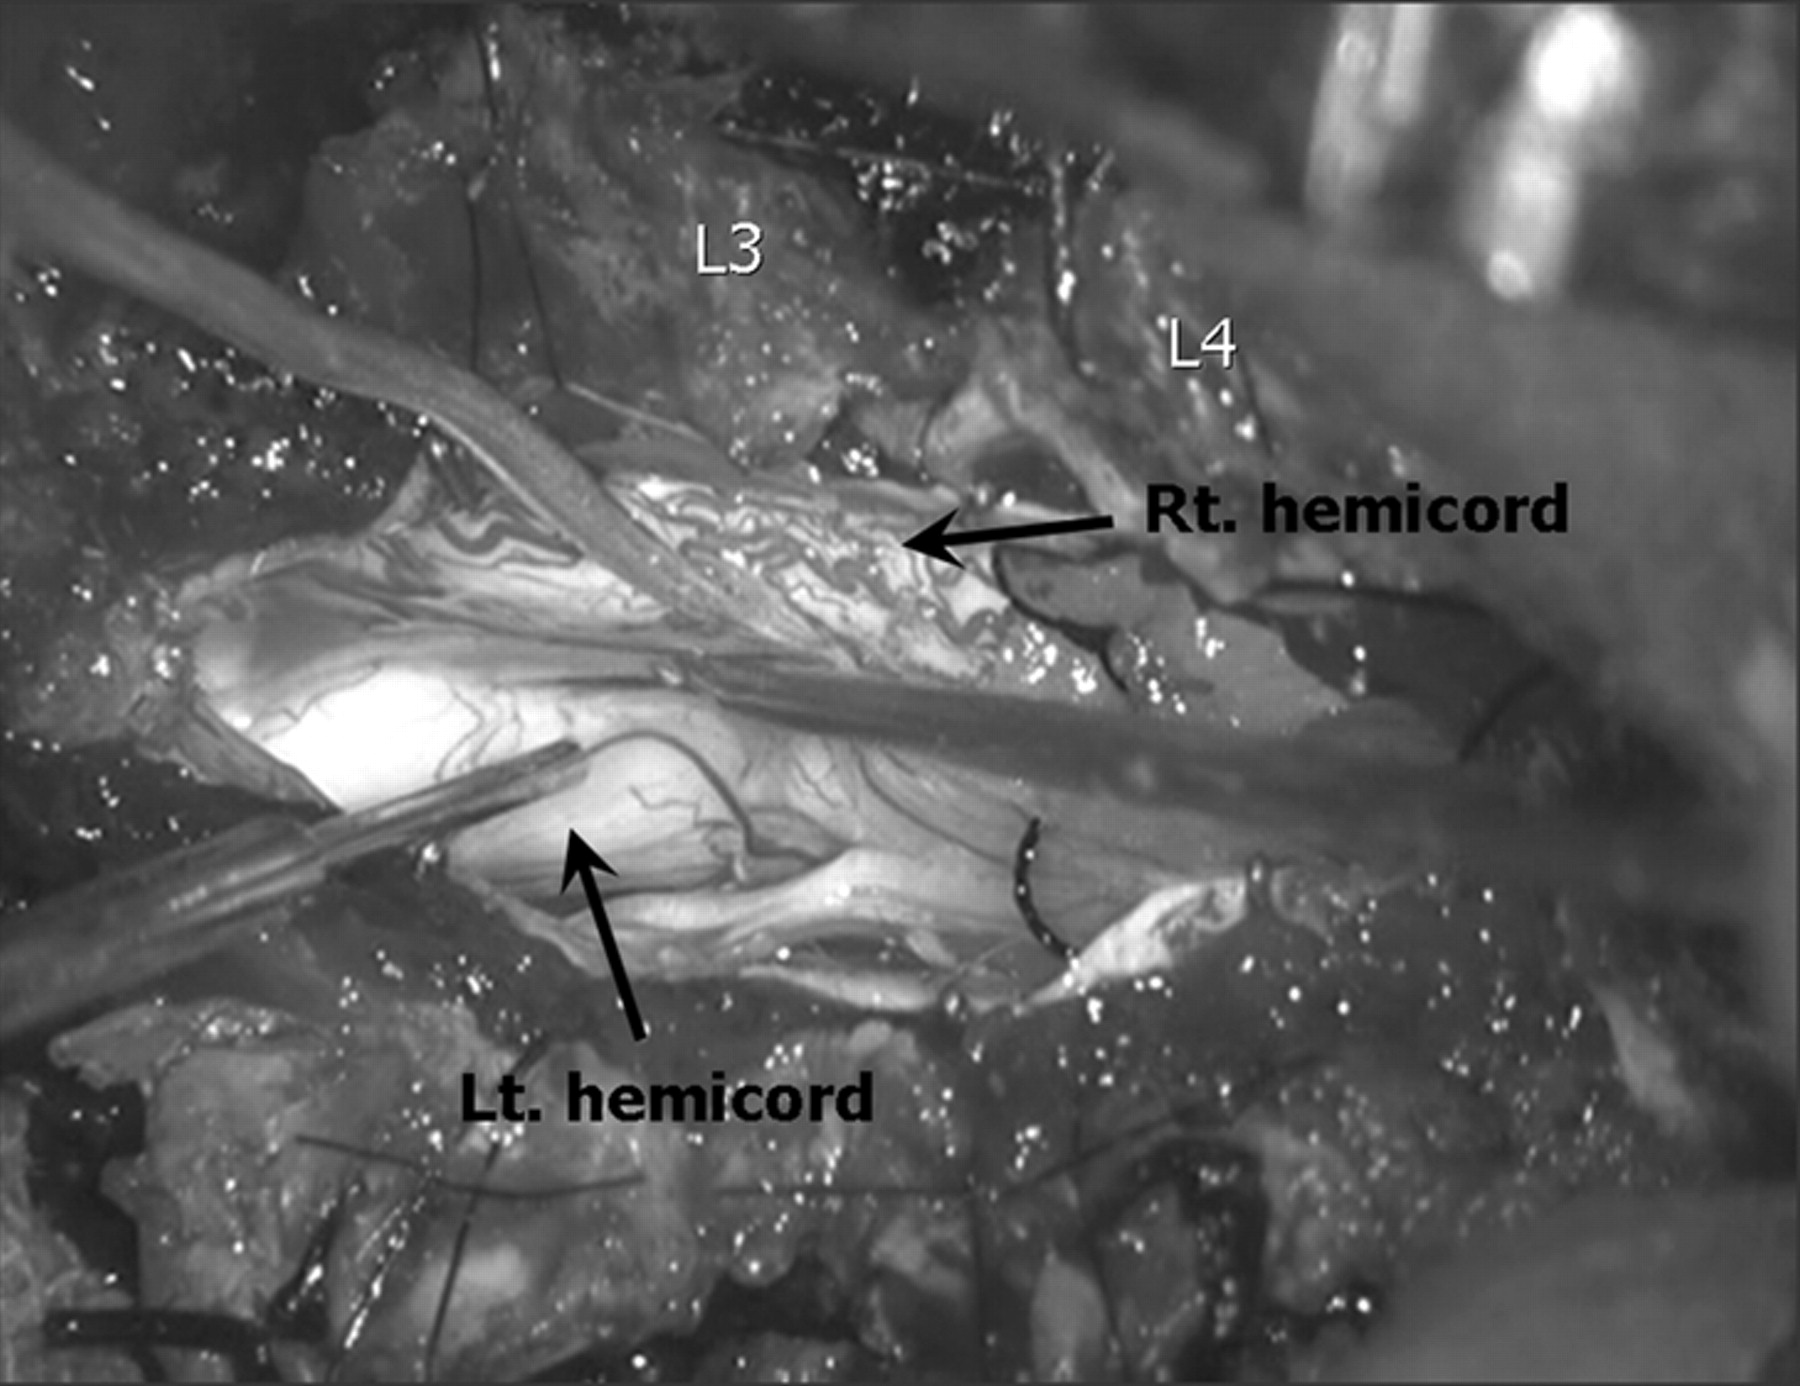

Surgery was performed to prevent the progress of the neurologic damage resulting from tethering of the cord. Surgery revealed an asymmetric duplication of the spinal cord, which was encompassed by the single dural sac, and no dural septum was recognized between either hemicord (Fig 5). Aberrant nerve roots were found along the lateral aspect of each hemicord. The proximal part of the left hemicord bent anteriorly and became smaller in diameter. Because laminectomies were performed from the level of L1 to L4, the inspection of the operating field was impossible at the spinal level of T12, and the exact intraoperative relation between the left hemicord and upper main spinal cord was not determined. Although somatosensory evoked potentials were not performed, the functional electrical stimulation studies revealed the visible movement of the left lower limb and anal muscles evoked by the electrical stimulation of the left hemicord, which suggests the efferent pathway that connects to the left hemicord from the main spinal cord. The nerve roots appeared slightly adherent to the dura at the L4–5 level, and the resection was made because the cord was tethered at the level of the lesion. The patient had an uneventful postsurgical recovery.

Photograph of the intraoperative surgical field shows an asymmetric duplication of the spinal cord, which is encompassed by the single dural sac.